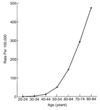

What is the epi of colorectal cancer?

- Most common GI malignancy; mortality 2nd only to lung cancer

- Higher incidence in developed countries: thought to be 2o to high fat, low fiber diet

-

Calcium and folate in diet may be protective

1. Folate may have anti-cancer benefit early in adenoma sequence - Most colorectal tumors are adenocarcinomas

- Incidence of CRC has declined 30% in last decade in patients >50-y/o

1. 5% of Americans will develop CRC and 40% of these will die of the disease - NOTE: cancer of sm. intestine very rare